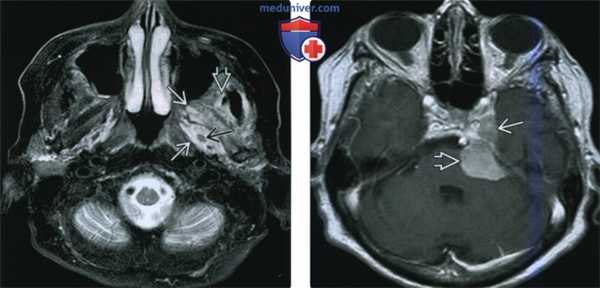

(Слева) МРТ Т2ВИ FS, аксиальная проекция. Наблюдается повышенная интенсивность сигнала крыловидных мышц и глубокой части височной мышцы. Затемнение ячеек сосцевидного отростка говорит о дисфункции слуховой трубы вследствие паралича мышцы, напрягающей небную занавеску. У этого пациента была обнаружена менингиома, локализующаяся в тройничной полости (здесь не отображена).

(Справа) МРТ Т1ВИ FS с КУ, коронарная проекция, этот же пациент: умеренное накопление контраста в крыловидных мышцах и уменьшение в размерах трубного валика. Такие находки говорят о подострой денервационной атрофии нижнечелюстного нерва. (Слева) МРТ Т1ВИ, коронарная проекция. Хроническая жировая атрофия левой височной и жевательной мышц? которая говорит о хроническом повреждении нижнечелюстного нерва. По сравнению со здоровой стороной левая челюстно-подъязычная мышца также уменьшена в размерах, имеется незначительная жировая инфильтрация.

(Справа) МРТ Т1ВИ в аксиальной проекции, этот же пациент. Правая челюстно-подъязычная мышца и подкожная мышца шеи интактны. Их отсутствие/сильная атрофия слева говорят, что повреждены и нижнечелюстной (челюстно-подъязычная мышца), и лицевой (подкожная мышца шеи) нервы.

(Слева) МРТ Т1ВИ в коронарной проекции. Справа переднее брюшко двубрюшной мышцы и подкожная мышца шеи интактны. Слева челюстно-подъязычная мышца и подкожная мышца шеи визуализируются плохо, что является следствием хронического повреждения нижнечелюстною и лицевою нервов, соответственно.

(Справа) МРТ Т1ВИ в аксиальной проекции, тот же пациент. Справа переднее брюшко двубрюшной мышцы и подкожная мышца шеи интактны. Слева обе мышцы подверглись жировой атрофии и из-за этого не видны. У пациента была обнаружена опухоль основания черепа, затрагивающая овальное отверстие и коленчатую ямку.

(Слева) МРТ Т1ВИ FS с КУ, коронарная проекция. Аденокистозная карцинома, которая распространяется в полость черепа через овальное отверстие. Подострая денервация жевательной мышцы сопровождается накоплением в ней контрастного вещества.

(Справа) МРТ Т1ВИ FS в аксиальной проекции, тот же пациент. Накопление контраста в жевательной и латеральной крыловидной мышцах, характерное для подострой денервации. Объем мышечной ткани начинает снижаться, что говорит о том, что подострая стадия подходит к концу.

(Слева) МРТ Т2ВИ FS, аксиальная проекция. На Т2 сигнал гиперинтенсивный, крыловидные и височная мышцы отечны, что говорит об острой-подострой стадии денервации. На этом срезе нижнечелюстной нерв выглядит как структура пониженной интенсивности, располагающаяся в жевательном пространстве.

(Справа) МРТ Т1ВИ с КУ в аксиальной проекции, тот же пациент. Причиной денервации является менингиома, расположенная в области пещеристою синуса и предмостовой цистерны. Шваннома тройничного нерва выглядит аналогично.